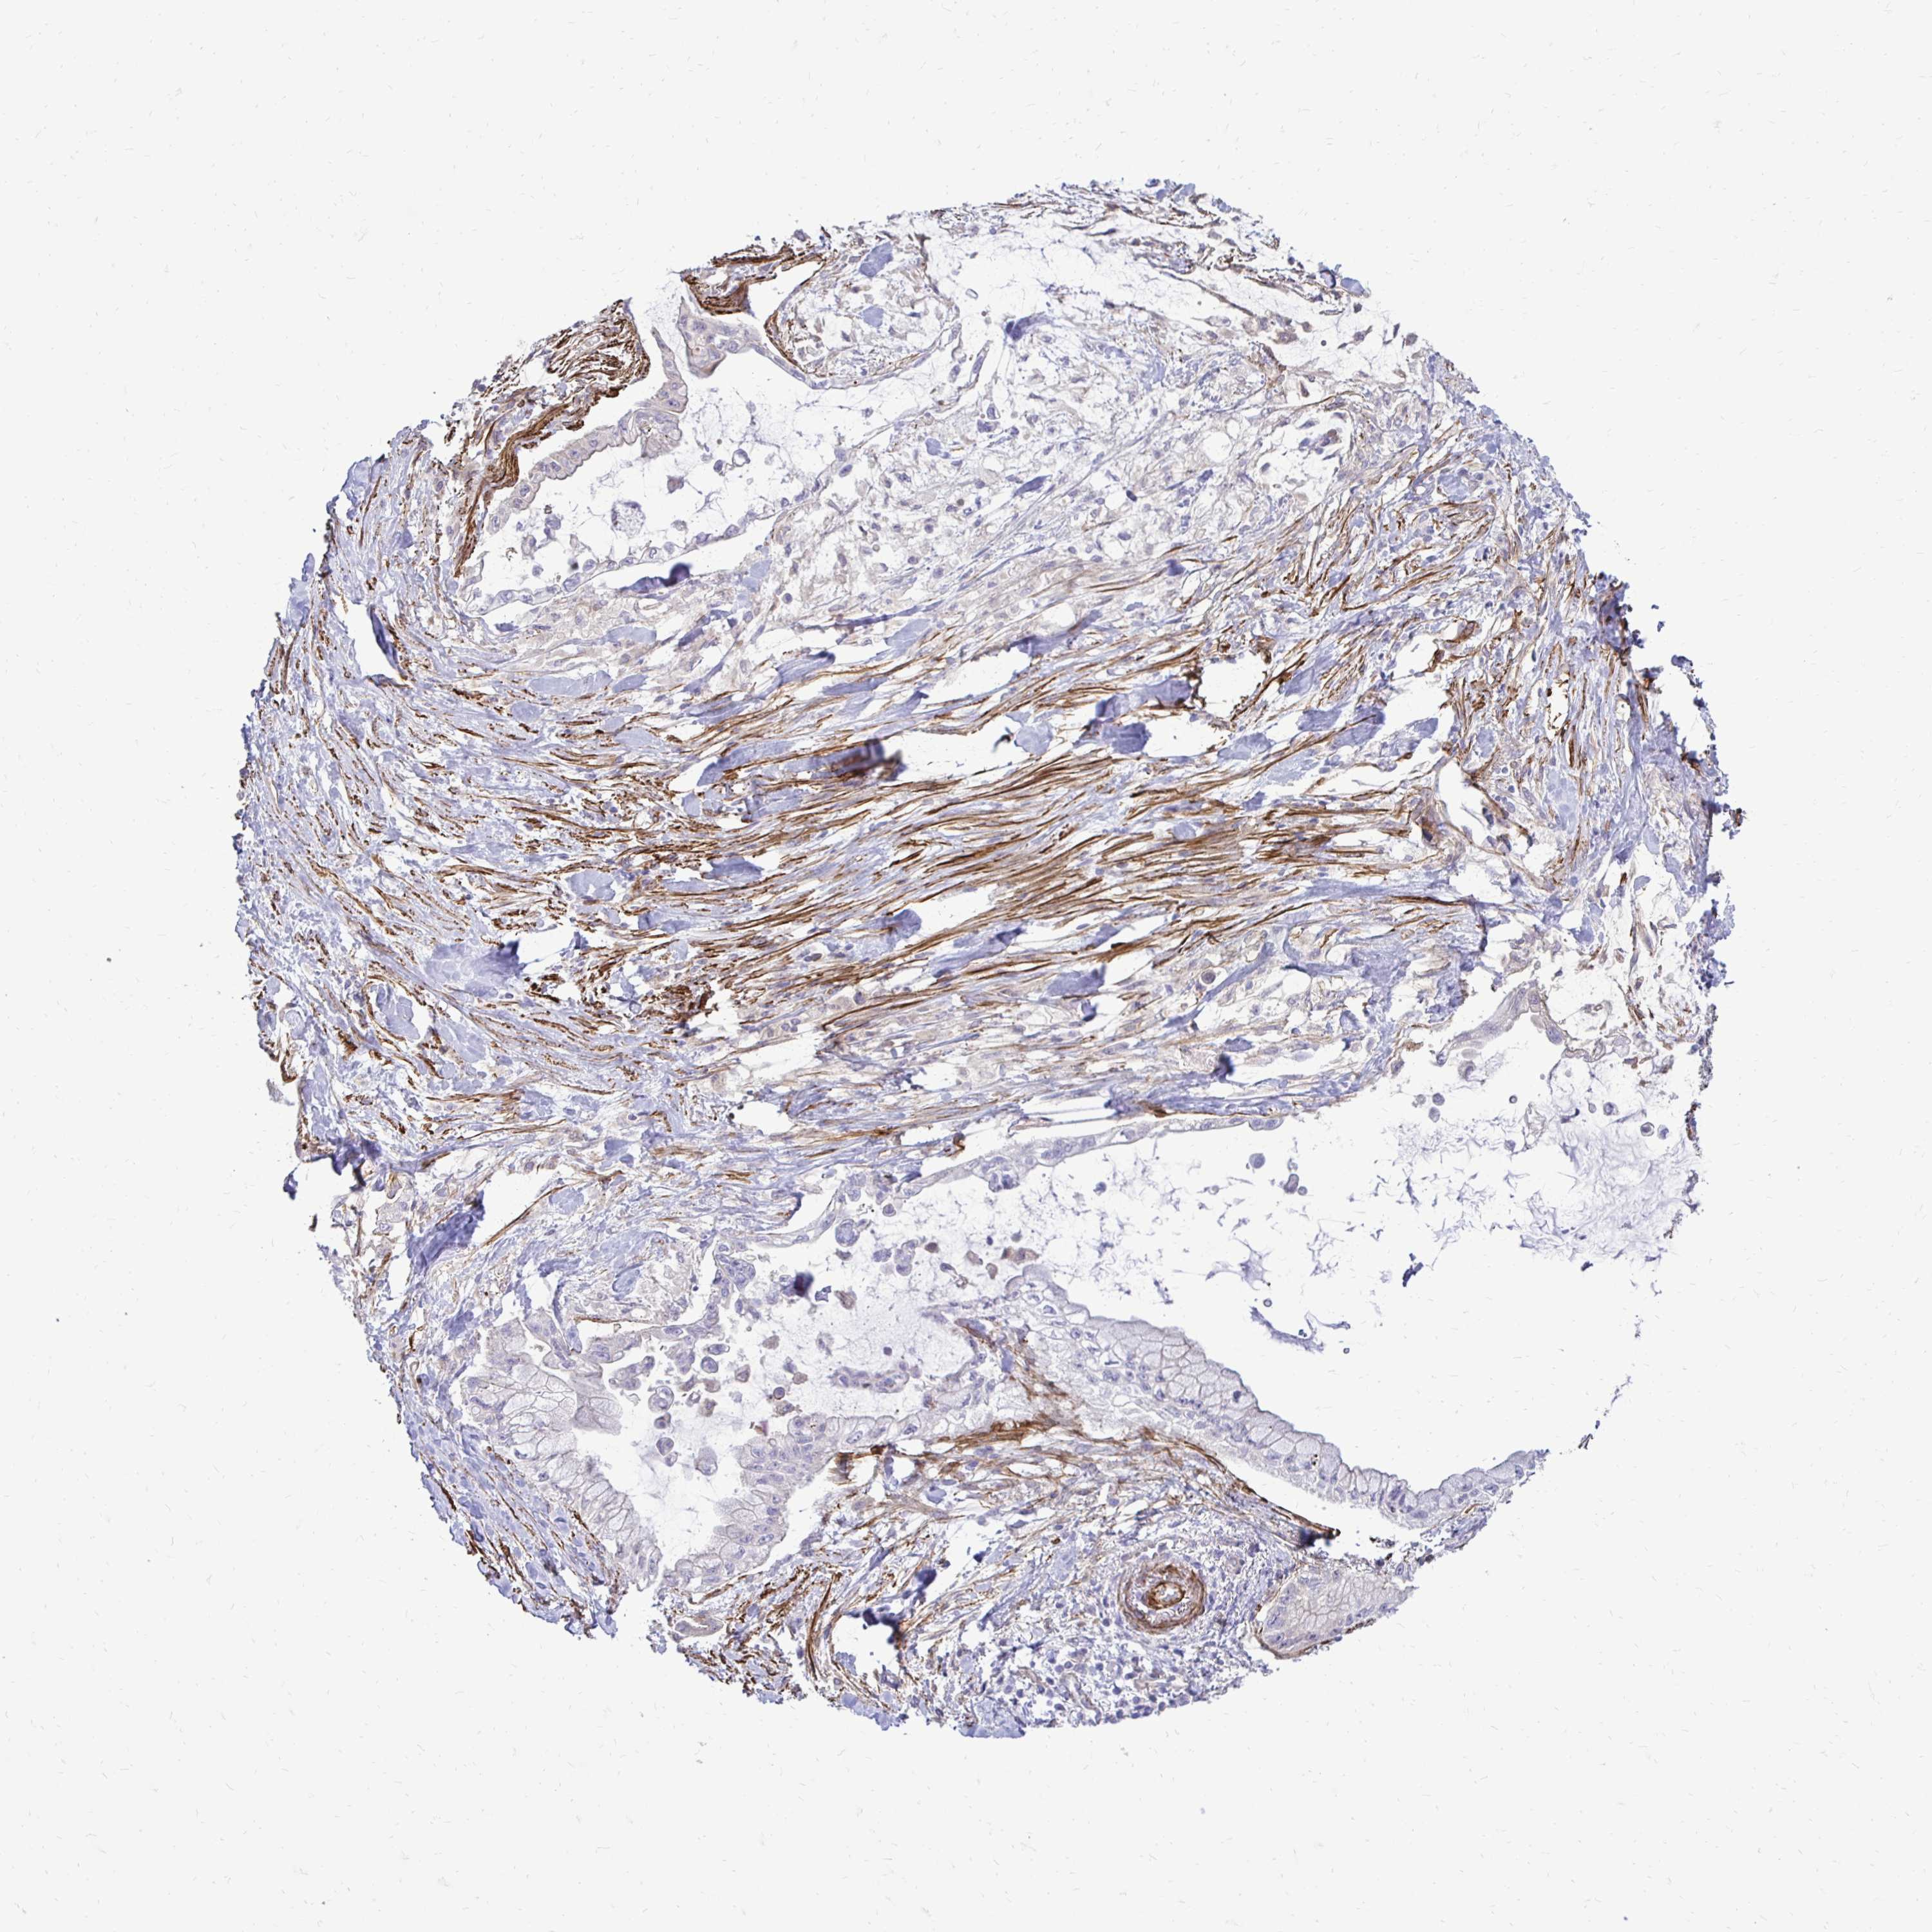

PANCREATIC CANCER - Protein expressioni

A mouse-over function shows sample information and annotation data. Click on an image to view it in a full screen mode. Samples can be filtered based on level of antibody staining by selecting one or several of the following categories: high, medium, low and not detected. The assay and annotation is described here.

Note that samples used for immunohistochemistry by the Human Protein Atlas do not correspond to samples in the TCGA dataset.

Antibody stainingi

Antibody staining in the annotated cell types in the current human tissue is reported as not detected, low, medium, or high, based on conventional immunohistochemistry profiling in selected tissues. This score is based on the combination of the staining intensity and fraction of stained cells.

Each image is clickable and will lead to virtual microscopy that enables deeper exploration of all samples and also displays staining intensity scores, fraction scores and subcellular localization as well as patient and tissue information for each sample.

Antibody HPA051322

Antibody CAB017111

Staining

High

Medium

Low

Not detected

Intensity

Strong

Moderate

Weak

Negative

Quantity

>75%

75%-25%

<25%

None

Location

Nuclear

Cytoplasmic/membranous

Cytoplasmic/membranous,nuclear

Adenocarcinoma, NOS